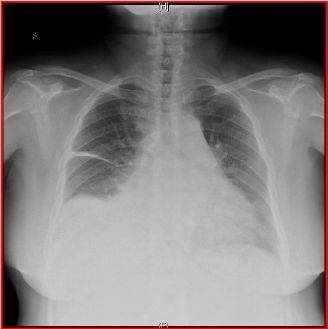

胸片(见图7):门诊胸片提示心影增大,肺淤血;右叶间积液;右膈抬高,右侧胸腔积液;双侧胸膜肥厚。

图7:门诊胸片提示心影增大,肺淤血;右叶间积液;右膈抬高,右侧胸腔积液;双侧胸膜肥厚